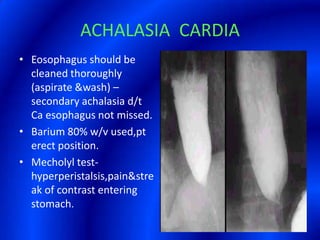

This document provides information about a barium swallow procedure. It begins with an introduction and overview of the embryology and anatomy of the pharynx and esophagus. It then describes the procedure itself, including preparation, technique, views obtained, and indications. Specific conditions that may be examined include pharyngeal and esophageal webs, foreign body impaction, scleroderma, dysphagia, mediastinal masses, and carcinoma. Diagrams are provided to illustrate normal anatomy and various pathological findings.